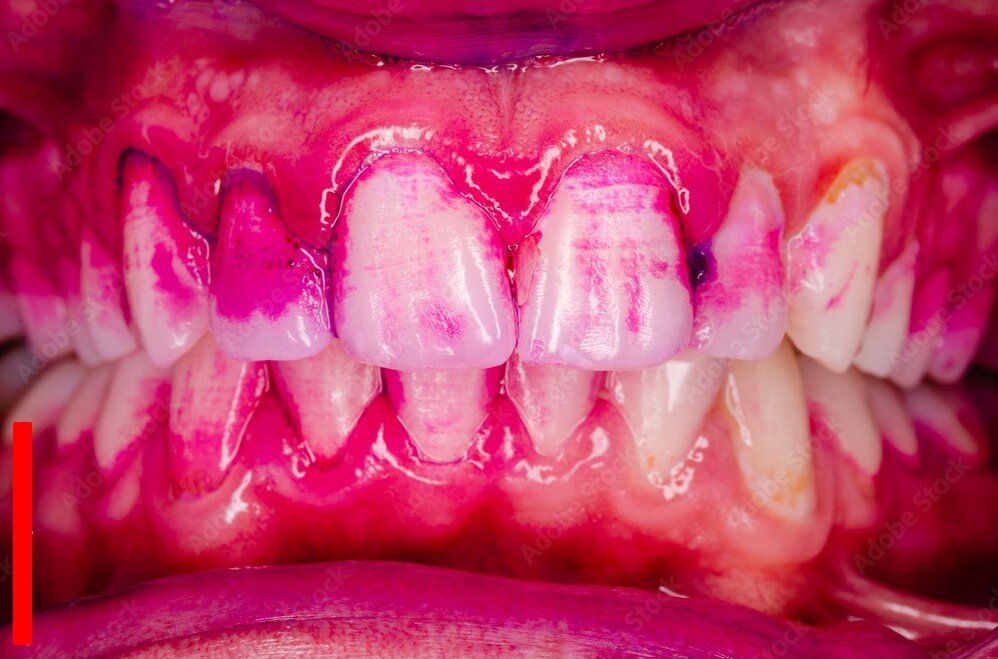

окрашенные участи зубов-зубной налёт

Зубной налёт-это скопление микроогранизмов нашей с вами ротовой полости. На зубах они прекрасно живут, множатся, питаются и собственно выделяют продукты жизнедеятельности.

-3

Продукты жизнедеятельности микроорганизмов, по своей природе, являются кислотами. Именно воздействие этих кислот на эмаль зуба и вызывает кариес.